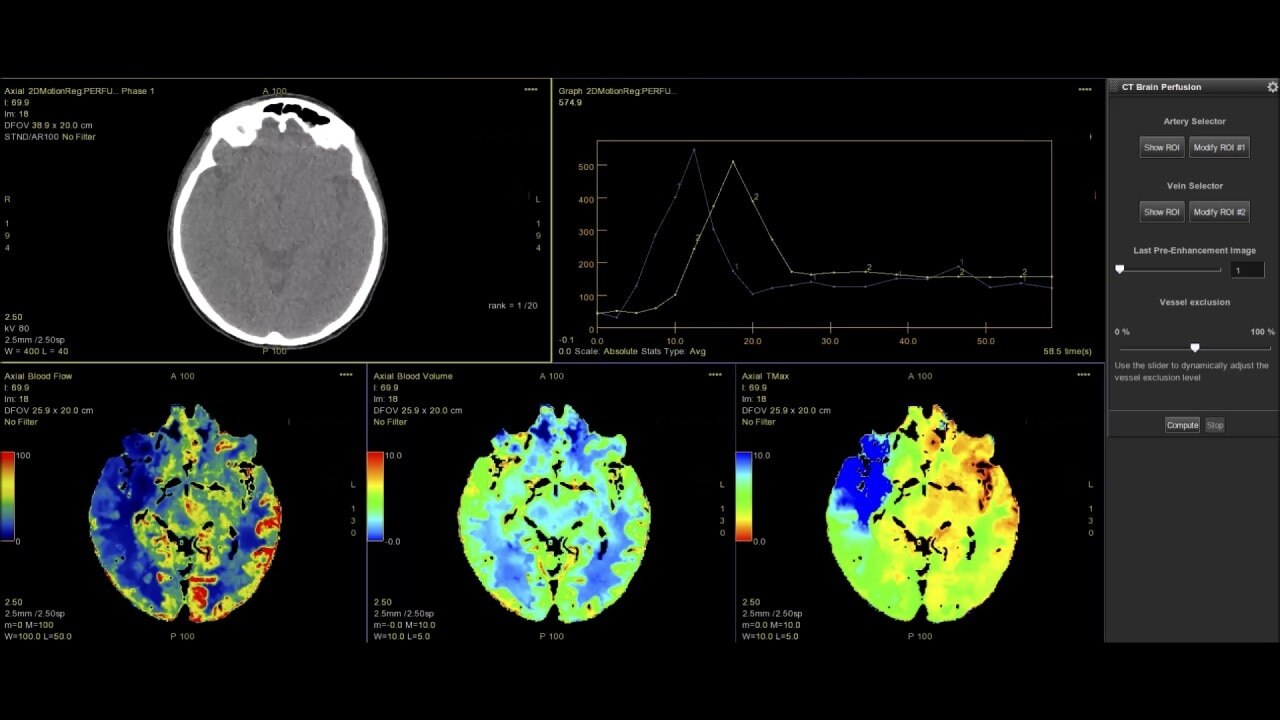

Dynamic CT Myocardial Perfusion Protocol

The dynamic myocardial perfusion protocol is laid out in a series of three easy to follow steps. Start by selecting the series that has been generated from the non-rigid registration protocol and then follow the guided workflow:

• Cardiac Reformat– images are automatically orientated into short and long axis views

• Segmentation–define the valve plane and the apex of the heart. The software will then calculate the endocardial and epicardial borders and provide a 17 segmented map of the myocardium along with a graphed view for each segment.

• Functional Maps – the third and final step produces the quantitative data with the color overlay and bullseye maps for blood flow, blood volume, mean slope of increase and mean transit time.